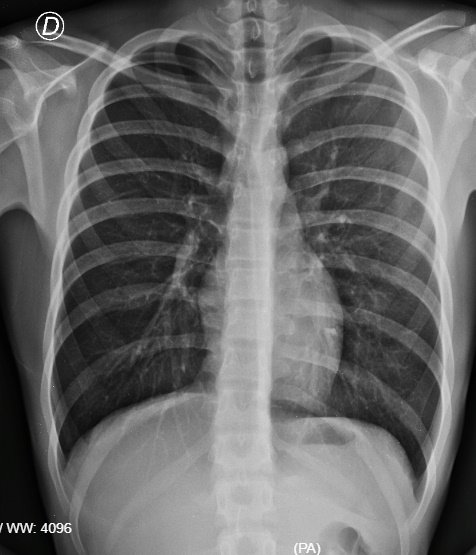

5. Parénquima Pulmonar

Órganos responsables del intercambio gaseoso hematosis. Los estudios de imagen recomendados para estos organos incluyen:

Tomografía Computarizada (10/10): Máxima resolución para la detección de nódulos y enfermedad intersticial.

Radiología Simple (7/10): Modalidad inicial para la evaluación de consolidaciones neumónicas.

Ecografía (5/10): Utilidad centrada en la detección de derrame pleural o neumotórax periférico.

Gammagrafía (6/10): Protocolo de ventilación-perfusión para el diagnóstico de tromboembolismo pulmonar.

Nota: La espirometría es la prueba fisiológica de referencia para determinar la capacidad ventilatoria.